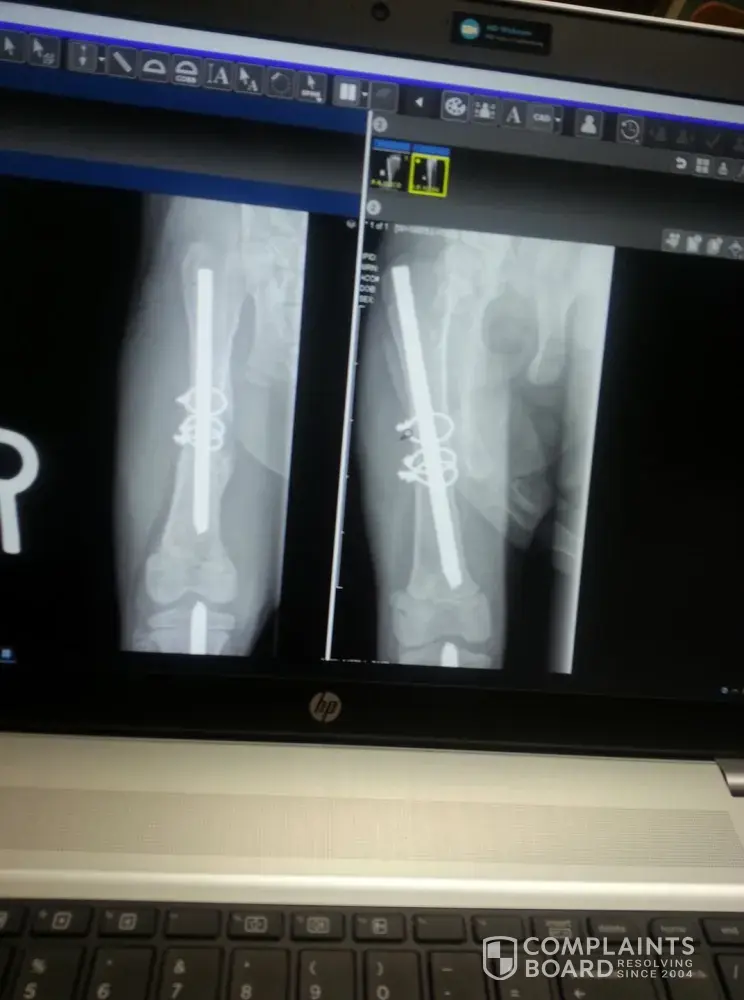

I can’t say enough about For the Love of Alex! If it wasn’t for Elizabeth’s unselfish love for all animals, our Joey wouldn’t be alive today! We found him in a frozen cornfield in December with several fractures on both of his legs, trying to make his way over the ice.